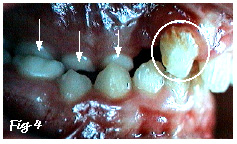

On notera enfin aussi, sur cette radiographie, l'ano-malie de la structure de l'émail de l'incisive centrale: il s'agit d'une hypoplasie de l'émail (cercle blanc, aussi sur Fig.4), autrement dit une anomalie de la minéralisation (calcification) de la couche superficielle de la dent (l'émail). Cette anomalie est fréquemment associée aux fentes alvéolaires (uni- ou bi-latérales).

Avant l'intervention, il faudra déterminer si un traitement orthodontique préliminaire est nécessaire. S'il l'est, c'est en général à cause de la présence d'un articulé dentaire croisé: on voit (Fig.4) les dents de l'arcade supérieure (du côté de la fente) s'articuler à l'intérieur (flèches) par rapport aux dents de l'arcade inférieure.